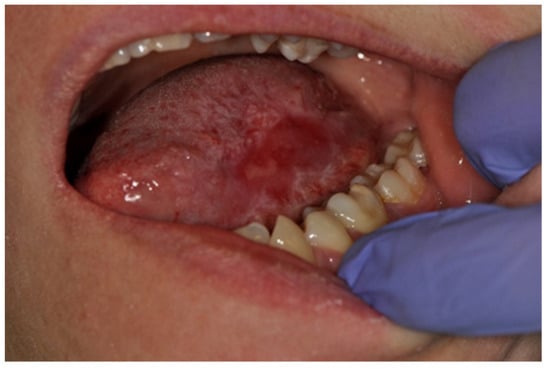

| Geographic tongue | 101 | 3.7 | 57.0 | 64 | 3.5 | 59.0 | 37 | 4.0 | 50.0 |